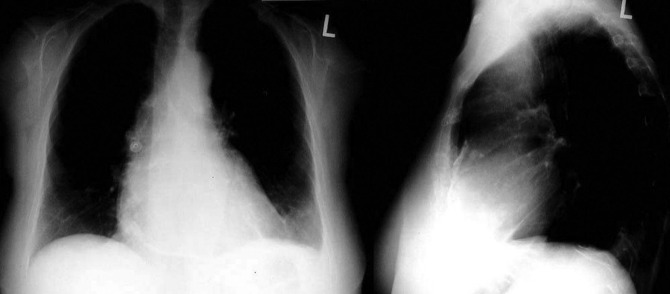

A pericardial effusion ( Figs. 16-1 to 16-15 ) is often suggested on the frontal chest radiograph by a smoothly distended, “flasklike” CPS. More than 500 mL of fluid must be present before the change in the CPS is fairly obvious. A flasklike appearance may be caused by myocardial disease as well; scrutiny of the hilar vessels may distinguish the two. In the presence of pericardial effusion, the hilar vessels are covered (the pericardium runs up onto them and obscures them). In the presence of myocardial disease, the hilar vessels are unusually prominent as they are distended under higher than usual pressure.

In a minority of patients with pericardial effusion, on the lateral radiograph, a stripe of radiolucent epicardial fat, a “fat line,” may be visible anteriorly, suggesting fluid in the pericardial space. A stripe greater than 2 mm is abnormal. This “pericardial stripe sign” is more easily seen in adults than children (more fat!).

A prominent azygous vein, superior vena cava, or inferior vena cava suggests cardiac tamponade.